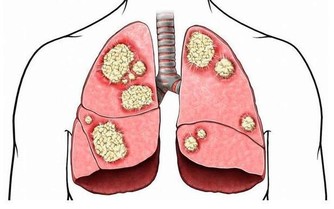

環境中的污染氣體吸收到了身體裡沒有排出去,這些一點點累積,就成了身體毒素。

綜上所述,身體毒素會對身體健康構成很大的威脅,很多疾病都與身體毒素息息相關。

只有排出身體毒素,才能提高我們的免疫力,使我們更好地迴避疾病的侵擾。